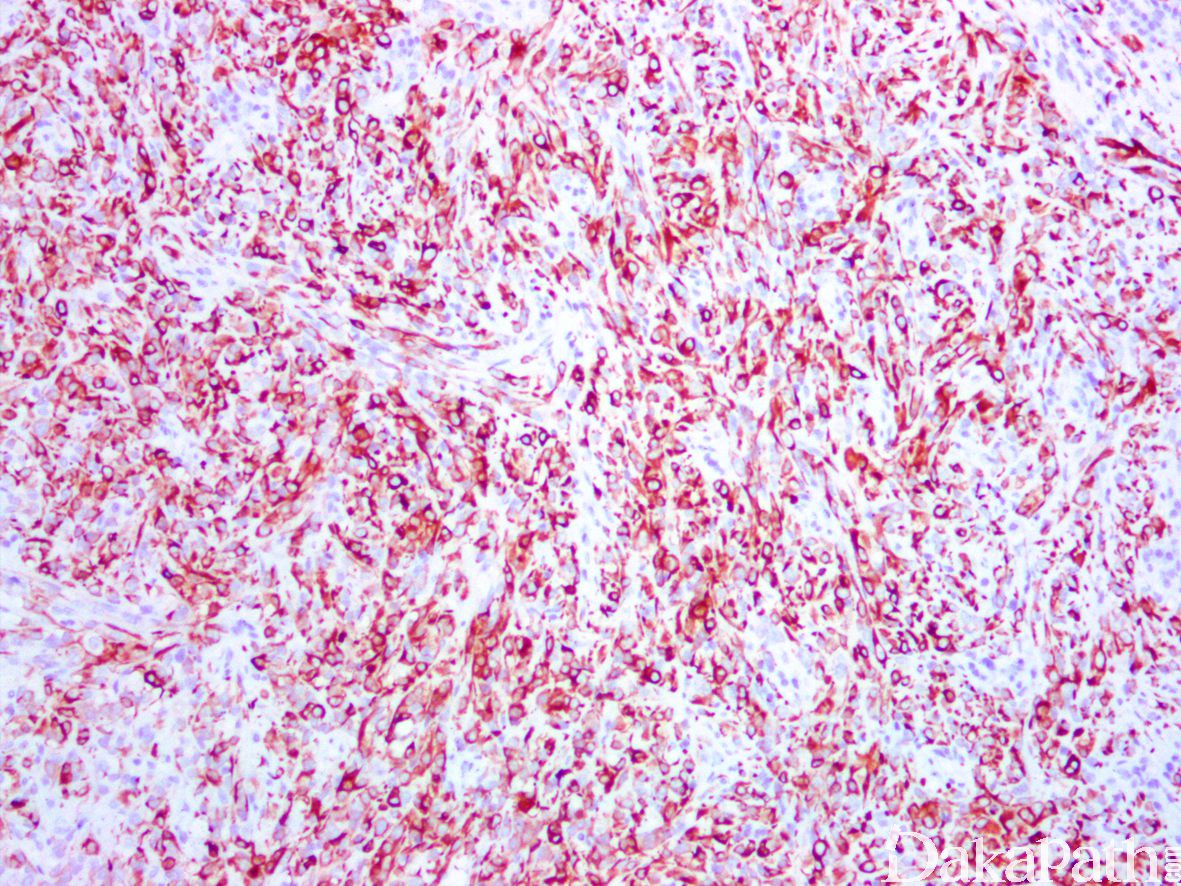

免疫组织化学染色:

desmin、MyoD 1 和 myogenin 常阳性。